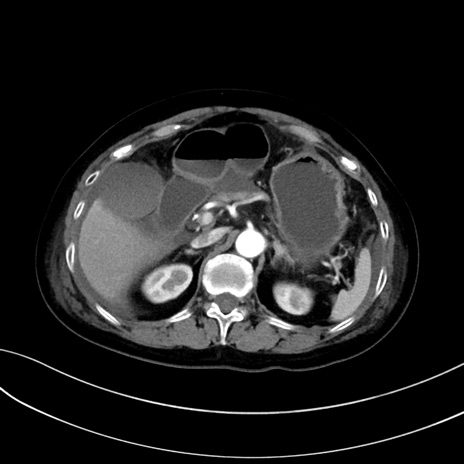

症例13 CT(横断像)1日半後